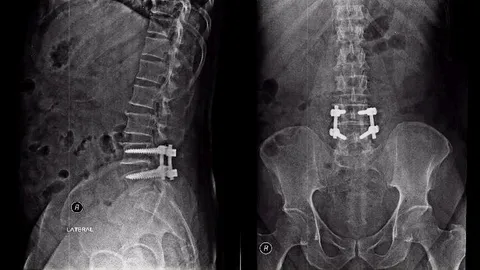

เทคโนโลยีใหม่ส่องกล้องผ่าตัดกระดูกสันหลัง